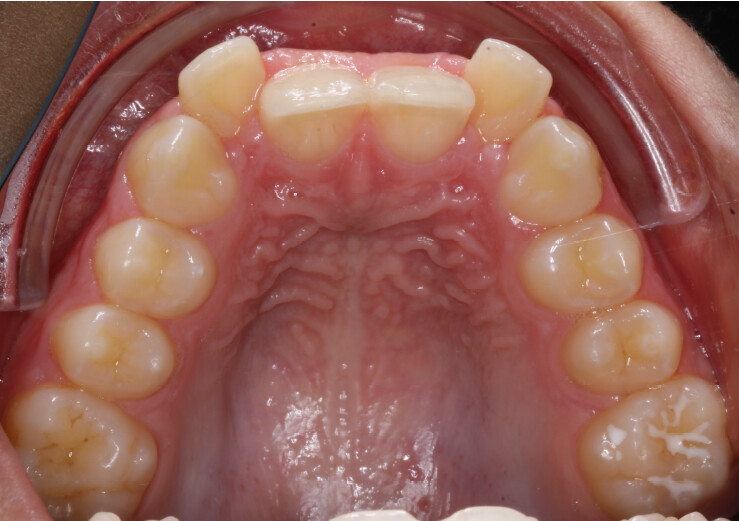

A 13-year-old male patient presented with a deep bite, characterized by near-complete coverage of the mandibular incisors. Clinical evaluation revealed bi-arch crowding, dental rotations, and proclination of the maxillary lateral incisors, contributing to the patient’s esthetic concerns. The facial profile was retrusive, consistent with mandibular retrognathism, and no significant periodontal abnormalities were detected.

The patient presented with a skeletal Class II relationship with bilateral molar and canine Class II and a Class II division 2 dental pattern. The deep bite was associated with anteroinferior crowding and an accentuated Curve of Spee. Facial analysis revealed good symmetry, a slightly increased lower facial third, and a convex profile characterized by mandibular and chin retrusion. Lip competence was mildly reduced, with a decreased nasolabial angle and mentalis hyperactivity, all of which compromised overall facial harmony.

- Programmed intrusion of the maxillary central incisors to reduce the gingival display and correct the gummy smile;